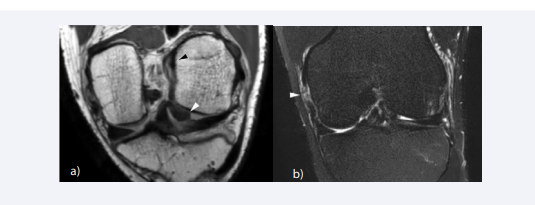

MR findings of ACL injury can be divided into primary signs related to the changes of the ACL itself, and secondary signs related to changes in the surrounding structures. The most reliable primary sign of acute ACL tear is the discontinuity of the ligament fibers, and the failure of the ACL fascicles to parallel the Blumensaat line on sagittal image [54] (Figure 2A).

Primary and secondary signs of ACL tear. (A) Sagittal T2-weighted image shows discontinuity of the ACL at the mid-substance indicating a complete tear. (B)  Sagittal fat-suppressed proton density-weighted shows diffuse enlargement and cloud-like hyperintense signal intensity of the ligament, resulting from edema and  hemorrhagic change of the ligament. (c) Sagittal image through the lateral compartment shows kissing bone contusion involving the posterior aspect of the lateral  tibial plateau and the mid portion of the lateral femoral condyle at the sulcus terminalis, which indicates a pivot shift injury. A slight depression fracture at the sulcus  terminalis of the lateral femoral condyle is noted (“deep notch sign”) (D) A thin fluid signal is interposed between the posterior horn of the medial meniscus and the  posteromedial capsule, leading to the diagnosis of meniscal ramp lesion associated with ACL tear.

Figure 2: Primary and secondary signs of ACL tear. (A) Sagittal T2-weighted image shows discontinuity of the ACL at the mid-substance indicating a complete tear. (B) Sagittal fat-suppressed proton density-weighted shows diffuse enlargement and cloud-like hyperintense signal intensity of the ligament, resulting from edema and hemorrhagic change of the ligament. (c) Sagittal image through the lateral compartment shows kissing bone contusion involving the posterior aspect of the lateral tibial plateau and the mid portion of the lateral femoral condyle at the sulcus terminalis, which indicates a pivot shift injury. A slight depression fracture at the sulcus terminalis of the lateral femoral condyle is noted (“deep notch sign”) (D) A thin fluid signal is interposed between the posterior horn of the medial meniscus and the posteromedial capsule, leading to the diagnosis of meniscal ramp lesion associated with ACL tear.

The ligament fibers may be edematous and hemorrhagic resulting in diffuse enlargement and cloud-like hyperintense T2 signal in the acute to subacute phase [55] (Figure 2B). The proximal stump of the torn ACL is usually oriented more vertically, and the distal stump more horizontally compared with the Blumensaat line. Nonvisualization of the ACL fibers is a common and specific finding of chronic complete tear of the ACL, resulting in an empty intercondylar notch [56, 57]. Another common finding of chronic ACL injury is a thin residual fiber demonstrating an abnormal slop. Occasionally, a chronic tear may be mistaken for an intact ligament, due to the fibrous scar that bridges the proximal and distal stumps giving the ACL a continuous appearance [55].

Various secondary signs may aid the diagnosis of ACL tears; anterior translation of the tibia, uncovering of the posterior horn of the lateral meniscus, buckling of the PCL, characteristic bone contusion patterns, and Segond fracture. Anterior translation of the tibia with reference to the femur is a helpful finding in diagnosing complete tears of the ACL [58] (Figure 3).

The pattern of bone contusions depends on the mechanism of injury and can be helpful in diagnosing associated injuries of the meniscus and other ligamentous structures. The most common bone contusion pattern is the kissing bone contusion involving the posterior aspect of the lateral tibial plateau and the mid portion of the lateral femoral condyle at the sulcus terminalis, which is associated with pivot shift injury [16] (Figure 2C). Pivot shift reciprocating bone contusions indicate the impaction of the femoral condyle on the posterior aspect of the tibial plateau during anterior translation. Less commonly, bone contusions can be noted along the posterior aspect of the medial tibial plateau and the medial femoral condyle. Contusions of the medial compartment are thought to result from a contrecoup injury at the point of reduction [17]. Stronger compressive forces at the time of injury may cause cortical depression fractures in the tibia and femur. A depression fracture at the sulcus terminalis of the lateral femoral condyle is termed “deep notch sign” and is known as an indirect sign of acute ACL tear [61] (Figure 2C). With a depth cut-off of 1.5mm, the deep notch sign has a specificity of 100%, sensitivity of 15.4%, positive and negative predictive value of 100% and 49.1% respectively [62]. The deep notch sign was originally described on radiograph but can also be noted on MRI [63].

The clinical significance of meniscal ramp lesions in patients with ACL tear has gathered attention in the past decade. Meniscal ramp lesions refer to the tear, disruption, or separation of meniscocapsular junction of the posterior horn of the medial meniscus, which usually occur after traumatic knee injuries. Undiagnosed ramp lesions may lead to knee instability (anterior translation and external rotational laxity), aggravation of medial meniscus posterior horn tear and accelerated degeneration of both the meniscus and the articular cartilage [96]. Therefore, it is important to recognize ramp lesions in patients sustaining ACL injury. On MRI, ramp lesions are noted as a thin fluid signal interposed between the posterior horn of the medial meniscus and the posteromedial capsule (Figure 2d).